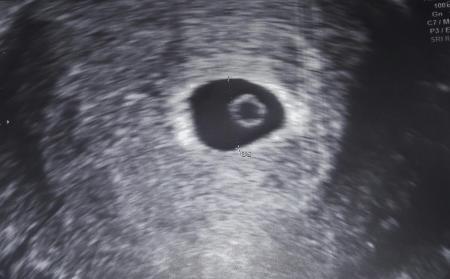

Hallo ihr lieben, ich war gestern bei.6+1 ssw beim Ultraschall..man konnte den Dottersack und die Fruchthöhle sehen..leider keinen Herzschlag oder Embryo. Ist das schlimm? Oder darf das sein? Der nächste Termin ist erst in 3 wochen:/